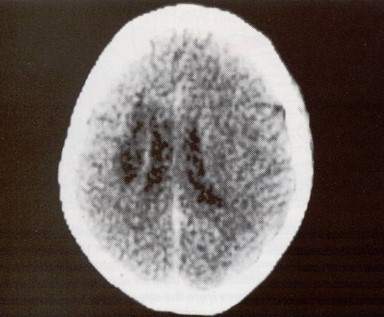

and the supranuclear nature of the lesion. The cause in this patient was a large infarct

of the internal capsule due to occlusion of branches of the left middle cerebral artery

(see below).

Infarction of the left internal capsule (CT scan, left image). Horizontal gaze pathways (illustration, right image).